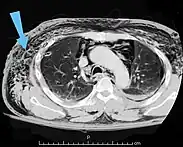

Significant cases of subcutaneous emphysema are easy to diagnose because of the characteristic signs of the condition.[1] In some cases, the signs are subtle, making diagnosis more difficult.[13] Medical imaging is used to diagnose the condition or confirm a diagnosis made using clinical signs. On a chest radiograph, subcutaneous emphysema may be seen as radiolucent striations in the pattern expected from the pectoralis major muscle group. Air in the subcutaneous tissues may interfere with radiography of the chest, potentially obscuring serious conditions such as pneumothorax.[18] It can also reduce the effectiveness of chest ultrasound.[27] On the other hand, since subcutaneous emphysema may become apparent in chest X-rays before a pneumothorax does, its presence may be used to infer that of the latter injury.[13] Subcutaneous emphysema can also be seen in CT scans, with the air pockets appearing as dark areas. CT scanning is so sensitive that it commonly makes it possible to find the exact spot from which air is entering the soft tissues.[13] In 1944, M.T. Macklin and C.C. Macklin published further insights into the pathophysiology of spontaneous Macklin's Syndrome occurring as a result of a severe asthmatic attack.

Bubbles of air in the subcutaneous tissue (arrow) feel like mobile nodules that move around easily